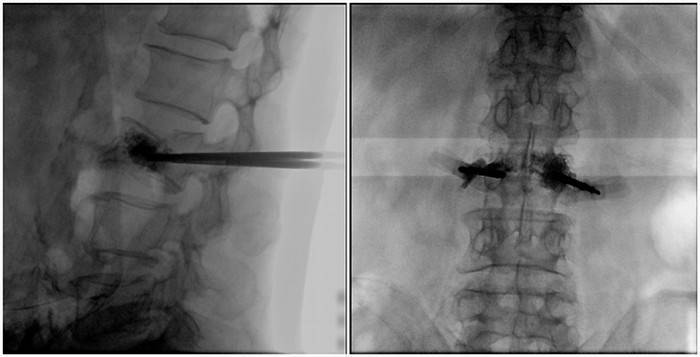

(2)術中切口5毫米,借助大視野平板C臂機PLX119C的高清圖像,確定進針的方向及進針的深度。經椎弓根向椎體置管,建立通道,插入骨擴張器(球囊)。球囊擴張恢復椎體高度,并在椎體內形成空腔,確定骨水泥的注入劑量,并注入骨水泥觀察其擴散情況。

大平板C臂機的高清圖像

(3)注射過程需要C臂透視來查看骨水泥的分布情況,預防骨水泥外露進入椎管內引起神經損傷。椎骨體內骨水泥填充完好以后,拔出工作套筒按壓止血,并繼續俯臥位十分鐘,等待骨水泥硬化,最終手術圓滿完成。